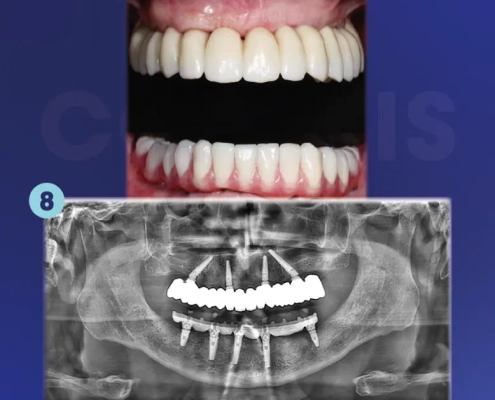

Cas clinique du Dr. Denglos avec les implants Co-axis®

La situation initiale montre un édentement complet bi-maxillaire avec axes implantaires défavorables et volumes osseux limités, compromettant la réalisation d’une réhabilitation implanto-portée transvissée sans correction d’angulation.

Avec la collaboration du Dr. Carl Denglos